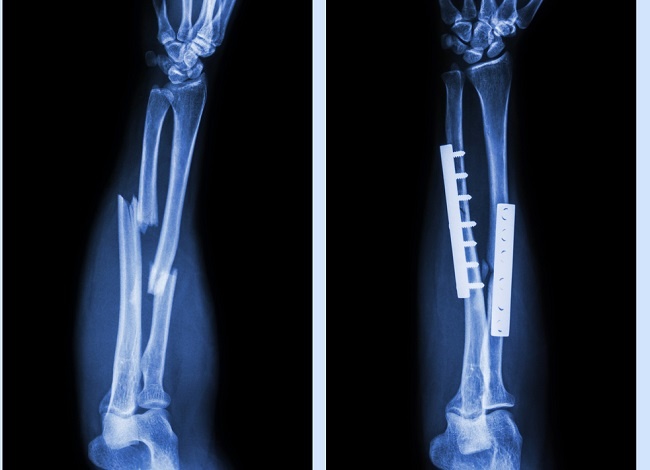

Pemeriksaan fisik menunjukkan adanya deformitas dan angulasi pada paha kiri, serta nyeri tekan di area tersebut. Analisis radiologis dilakukan untuk menilai kondisi tulang, dan hasilnya menunjukkan tidak adanya medula pada sinar-X femur. Gambar radiografi mengungkapkan patah tulang femoral yang sangat terdislokasi dengan angulasi dan pemendekan yang signifikan. Ciri-ciri radiografis khas osteopetrosis, seperti peningkatan kepadatan tulang dan pola trabekular yang berubah, menyulitkan dalam karakterisasi patah tulang secara tepat.

Penanganan patah tulang pada pasien dengan osteopetrosis memerlukan pendekatan multidisipliner. Upaya reduksi tertutup di bawah panduan fluoroskopi mengalami kesulitan karena sifat tulang yang keras. Oleh karena itu, rencana perawatan meliputi penggunaan analgesik, imobilisasi dengan traksi kulit, dan ORIF dengan fiksasi plat.

Salah satu tantangan utama dalam melakukan ORIF pada tulang osteopetrotik adalah kekakuan tulang yang memerlukan tekanan pengeboran yang lebih tinggi, yang dapat meningkatkan risiko nekrosis. Dalam kasus ini, fiksasi plat yang terpasang pada bagian proksimal femur kiri menunjukkan efek kompresi yang baik pascaoperasi.